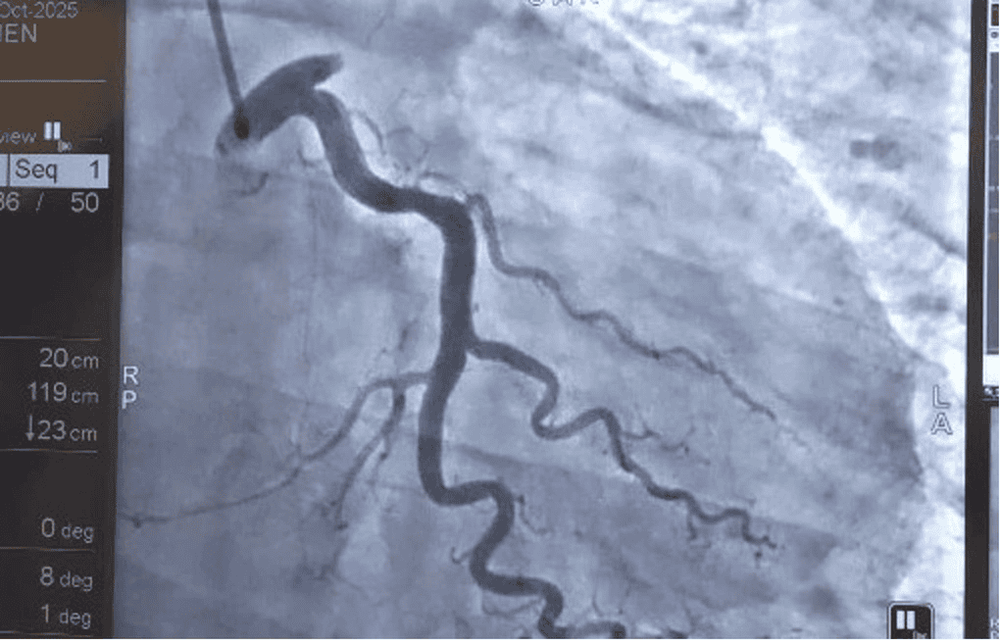

Hình ảnh hình chụp động mạch vành trái (Left Coronary Artery ) cho thấy tắc hoàn toàn ngay từ lỗ vào của động mạch liên thất trước (LAD) - một vị trí rất nguy hiểm

Các bác sĩ tiến hành hút huyết khối, loại bỏ khối máu đông gây tắc hoàn toàn lòng mạch, sau đó đặt stent phủ thuốc kích thước 4.0 x 48 mm để tái thông dòng máu nuôi cơ tim. Toàn bộ quá trình can thiệp kéo dài khoảng 80 phút, được thực hiện liên tục, chính xác và an toàn.